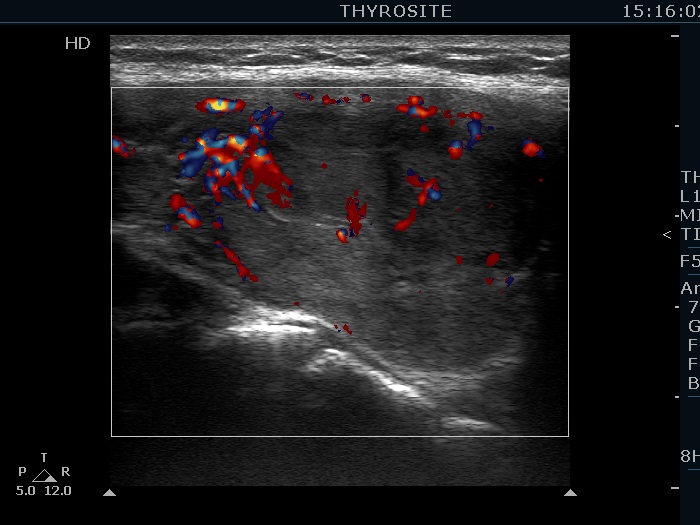

Left lobe, longitudinal scan, color Doppler mode.